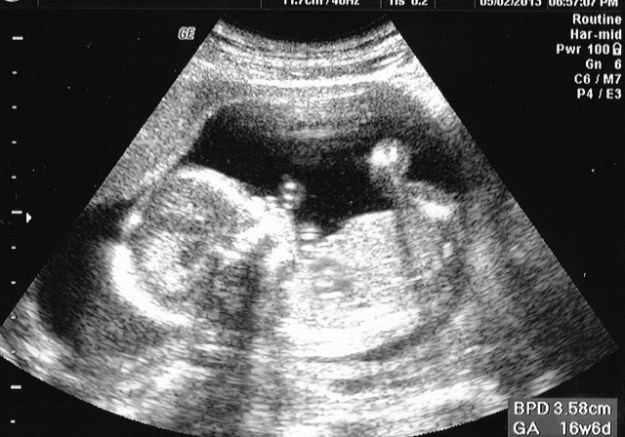

Coté bébé tout roule, j’ai enfin réussi à assister à l’echographie. Ecoute du coeur et bébé en mouvement, tout était parfait. Malgré ses 11.7 cm, le medecin a été incapable de nous dire si c’était un garcon ou une fille, c’est encore un peu trop tot (j’ai pour ma part eu l’impression de voir passer une petite paire de t*sticules à l’écran, mais je ne suis pas un professionnel des echographies, donc je n’ai rien dit).

echo 16sa

Ne pas faire attention aux mesures sur l’écran, le medecin ne mesurait pas la taille du bébé.